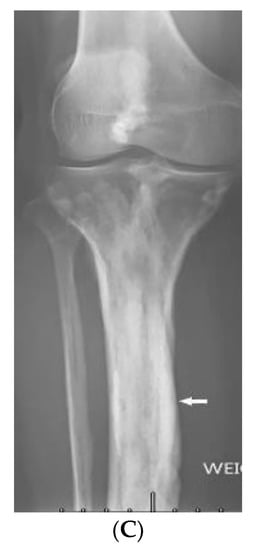

3.9. Fong Disease

| Fong (Nail–patella) syndrome | Hypoplastic nails, triangular lunulae Hypoplastic patellae Focal segmental glomerulosclerosisLester iris | Bilateral absence of patellae Posterior iliac horns (Fong’s prongs) Subluxation of radial heads |